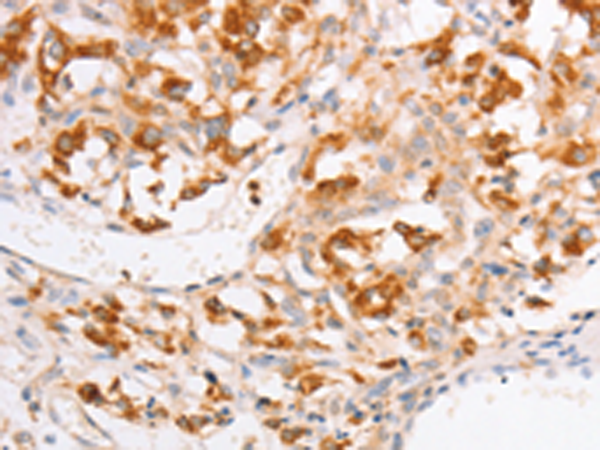

分类: 科研抗体货号: P07991别名: BB2; CD54; P3.58应用: WB,IHC反应种属: Human